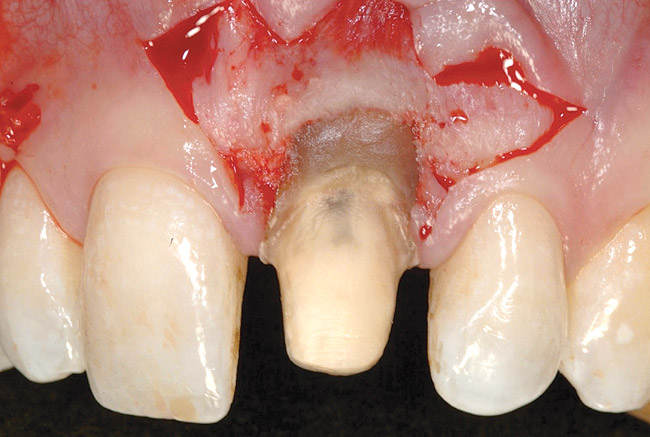

Before incision, the trimmed acellular dermal matrix was rehydrated in the PRP solution previously obtained. A broad-based, papillary spacing incision was made at the facial of tooth No. 9, followed by a full-thickness, muco­periosteal flap elevation. The facial root surface of the tooth exhibited notches and an uneven root surface. After extensive root planing of the facial root surface with hand planing and rotary instrumentation to eliminate not only the notched root surface but also the pre-existing facial tooth preparation margin, a new chamfer margin was prepared in the tooth 1 mm from the pre-existing margin (Figure 17). This was followed by application of a citric acid solution with a pH of 1 over the facial root surface for 1 minute to aid in sterilization of the root surface.6 Adjustment to the facial aspect of the pre-existing provisional restoration by shortening the facial margin by 1 mm was accomplished, and the provisional restoration was cemented with temporary cement (Figure 18).

Figure 17  Case Two Initial incision, prepared root surface, and margin alteration.

Figure 17